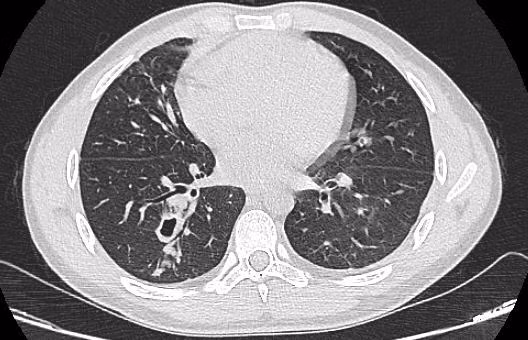

Hình ảnh phim chụp cắt lớp phổi của bệnh nhân sán lá phổi. Ảnh: BVCC.

Vừa qua, Bệnh viện Đa khoa Đức Giang tiếp nhận nam thanh niên quê ở Sơn La có các triệu chứng mệt mỏi, ho nhiều, ho ra máu, đi khám ở nhiều nơi không ra bệnh. Sau khi đến, các bác sĩ phát hiện, bệnh nhân nhiễm sán lá phổi.

Sán chủ yếu ký sinh trong phổi, làm nang trong tiểu phế quản nhỏ của phổi người hay súc vật. Trong mỗi nang hầu hết có 2 con và dịch mủ màu đỏ, xung quanh có mạch máu tân tạo. Trứng sán có màu nâu sẫm, hình bầu dục, bên trong có chứa phôi.